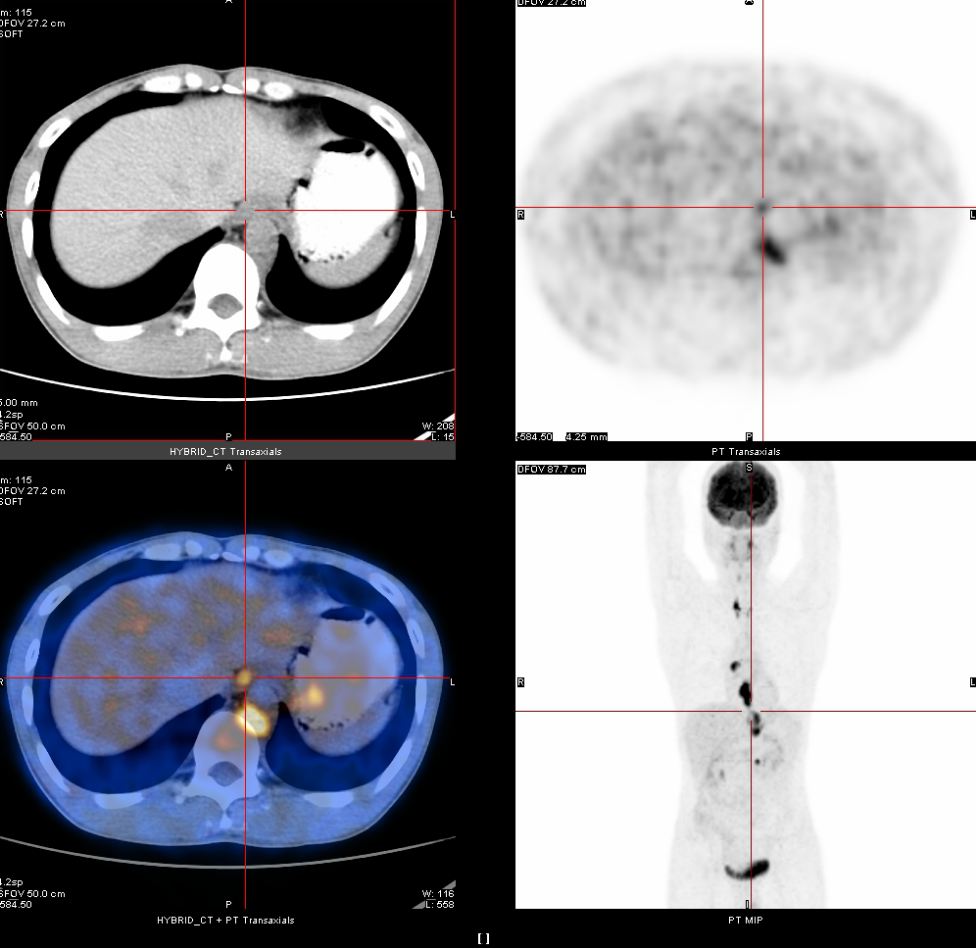

2020年3月13日

全身PET-CT示:1、食管胸中下段管壁不规则增厚,代谢增高,考虑食管癌。2、上纵隔胸廓入口区气管两旁、右下肺静脉后方、贲门区、肝胃间隙、降主动脉后方、膈肌脚后方、腹膜后腹主动脉左旁(左肾门下方平面)见多发高代谢肿大淋巴结,考虑淋巴结转移,建议随访复查。3、右肺上叶前段胸膜下小结节影,代谢未见增高,建议随访复查。4、右肺下叶外基底段条索影,考虑慢性炎性改变。5、双侧上颌窦轻度慢性炎症。6、双侧颈部多发小结节影,代谢未见增高,考虑淋巴结慢性炎性增生。7、肝左叶内侧段小钙化灶。